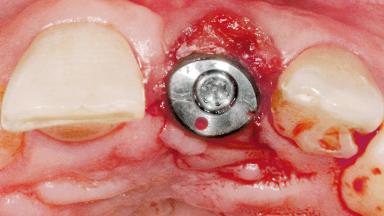

Late Flapless Placement of an Implant in a Maxillary Left Central Incisor Site

Type of Implants One-Piece

Attachment One-Piece

Abutment Type Standard

Prosthesis Type FDP

Placement Protocol Early or late implant placement